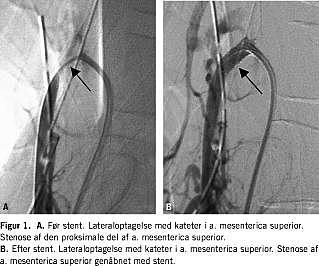

Efter 29 dages indlæggelse blev patienten overflyttet til en specialiseret medicinsk gasteroenterologisk afdeling til videre udredning og behandling. Grundet forværret almentilstand med peritoneal reaktion foretog man samme dag eksplorativ laparotomi. Man fandt hele tyndtarmen iskæmisk med spredte nekroser og uden peristaltik. Højre side af colon var let injiceret. Galdeblæren var nekrotisk. Der var ingen puls i a. mesenterica superior. Man foretog kolecystektomi. Umiddelbart efter operationen blev der foretaget akut abdominal arteriografi. Her fandt man okklusion af truncus coeliacus, a. mesenterica superior og stenose af a. mesenterica inferior. Dagen efter foretog man PTA med stentanlæggelse i truncus coeliacus og a. mesenterica superior. Figur 1A viser stenosen i a. mesenterica superior, Figur 1B viser a. mesenterica superior efter stentanlæggelse og ballondilatation (PTA). Tilsvarende gjorde man i truncus coeliacus. Herefter fandt man normalt flow i begge kar. En laparotomi med second look samme døgn viste hyperæmisk tyndtarm med peristaltik og tre nekrotiske områder, der blev oversyet. Der var postoperativt et kompliceret forløb med tarmperforation, tarmresektion af 10 cm tyndtarm og anlæggelse af høj aflastende jejunostomi. Grundet høj stomi blev patienten sat i fuld parenteral ernæring postoperativt.